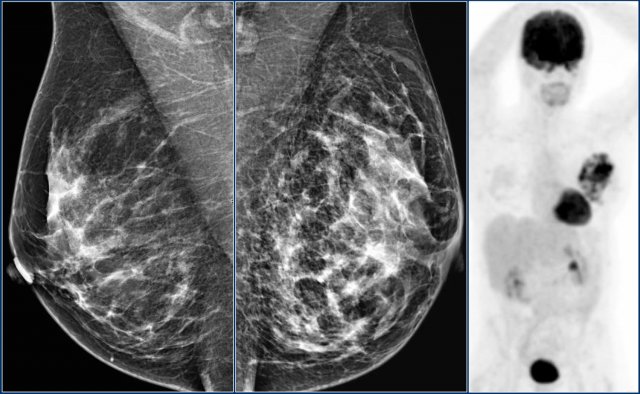

Here an example of global asymmetry.

In this patient this is not a normal variant, since there are associated features, that indicate the possibility of malignancy like skin thickening, thickened septa and subtle nipple retraction.

Ultrasound (not shown) detected multiple small masses that proved to be adenocarcinoma.

The PET-CT shows diffuse infiltrating carcinoma.